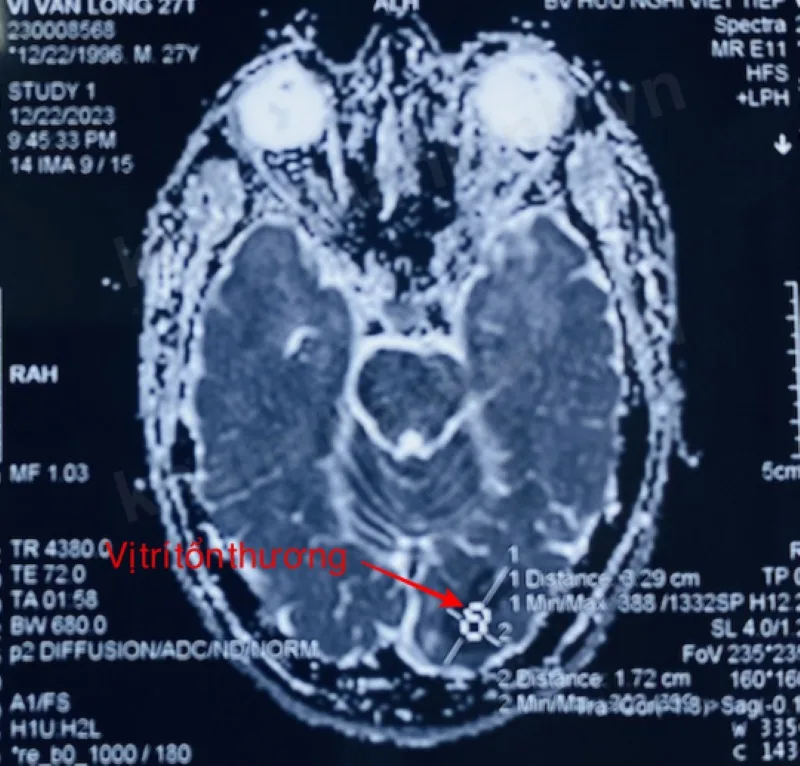

Người bệnh đã được nhập viện tại Bệnh viện Hữu nghị Việt Tiệp trong tình trạng thị lực mắt phải 8/10 (bán manh đồng danh), soi đáy mắt và mắt trái bình thường, kết quả chụp cộng hưởng từ sọ não cho thấy hình ảnh nhồi máu não mới thuỳ chẩm bên trái.